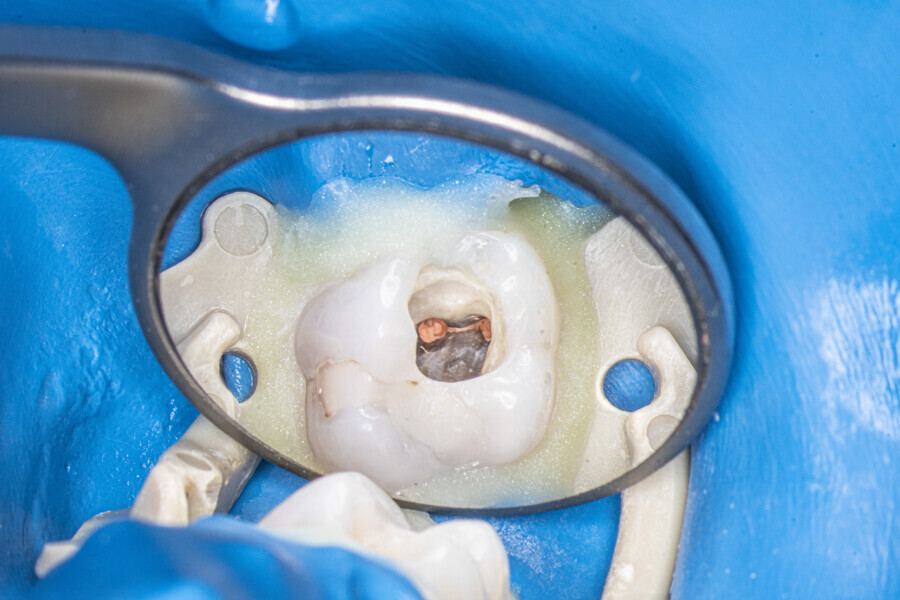

The first trials of the LPE concept were performed on extracted human molars. Although the dynamics of fluid during root canal irrigation are completely different in vivo than in extracted teeth, these kinds of trials provide initial information about the procedure. Some of these teeth had apices closed with a coat of wax and composite resin to close the apical delta and simulate the periapical tissue. After creation of the access cavity, the pulp chamber was cleaned with continuous irrigation with 5.25% NaClO activated with a SkyPulse laser (Fotona) in AutoSWEEPS mode (20 Hz, 15 mJ). A 25/0.07 reciprocating file (Shenzhen Perfect Medical Instruments) was used to perform the pre-flaring procedure. After opening the coronal third, continuous irrigation with 5.25% NaClO activated with the laser was used to clear the debris for 30 seconds. After removing the debris, a #10 C-PILOT file (VDW) was used to establish apical patency, without forcing the file if possible. In some cases, apical patency was reached already at this stage of root canal preparation. In all cases, the second step of instrumentation was the preparation of the middle third with the same file, and the same irrigation procedure was performed. Subsequently, the C-PILOT file was used to reach the apical foramen. At this stage, apical patency was reached in most cases, but in some roots, there was no possibility of entering the apical foramen. The working length was confirmed with a radiograph with the hand file. Usually, the next procedure to be done is apical preparation, but the LPE concept is based on an enhanced irrigation protocol. Following this protocol, irrigation was performed for 5 minutes with continuous flow of 5.25% NaClO activated with the SkyPulse laser in AutoSWEEPS mode (20 Hz, 20 mJ) with a conical sapphire fibre. The next step was alternating irrigation with 17% EDTA for 30 seconds, with 5.25% NaClO for 30 seconds and with 17% EDTA for 30 seconds, all activated with AutoSWEEPS, followed by irrigation for another 5 minutes with 5.25% NaClO activated with AutoSWEEPS. In most cases, the next step after this stage of enhanced irrigation was the calibration of the apical constriction rather than apical preparation per se, but this step requires further investigation.

At the second appointment, the temporary restorations were removed, and the chlorhexidine was washed out with sterile water and EDTA. After opening the orifice of the MB2 canal in the first molar, the operator was not able to reach patency in the canal. Therefore, the isthmus between the MB1 and MB2 orifices was opened with diamond-coated ultrasonic tips. Finally, patency was reached. Shaping the MB2 canal in the second molar was possible only to the place of the junction with the MB1 canal. The CBCT imaging had revealed previously that the MB2 canal should have its own lumen in the apical third, but the place of the junction was below the curvature. The possibility of locating this space without damaging the root was very poor. At this stage, the LPE enhanced irrigation protocol was performed again. After performing of the irrigation protocol, the apical preparation was performed for all the canals. The final irrigation protocol was performed with 5 minutes of constant flow of 5.25% NaClO for 2 minutes, alternating with 17% EDTA for 30 seconds, with 5.25% NaClO for 30 seconds and 17% EDTA for 30 seconds, and irrigation with 5.25% NaClO for 5 minutes. All the irrigants were activated with an EDDY sonic tip (VDW). After performing the periapical radiographs, a CBCT scan was performed to confirm the separate path of the sealer that filled previously unprepared spaces of the MB2 canals in both teeth. In both cases, it was clearly visible on the CBCT image that all the previously unprepared spaces were filled with the obturation material.

A 30-year-old female patient presented to the office owing to pain related to the maxillary right first molar. The radiograph revealed a periapical radiolucency, indicating exacerbated chronic periapical periodontitis. The access cavity was created with the Safe Access and Preparation Concept burs set (manufacturer). The pulp chamber was cleaned with 5.25% NaClO activated with the SkyPulse laser. Four orifices were located, and all four canals were shaped in the same sequence described previously. The LPE enhanced irrigation was performed with activation by the SkyPulse laser. In the mesial root, a clean isthmus was visible, and the irrigants started to flow between the MB1 and MB2 canals in the apical third, which was confirmed with a micro-suction cannula. In the MB1, MB2 and DB canals, apical preparation was performed with Endostar E3 Azure files (Poldent) up to size 25/0.04 owing to the apical curvatures. In the DB canal, patency was not established. The final irrigation protocol was performed in the same sequence as described before. The periapical radiograph confirmed that the isthmus was filled with the sealer.